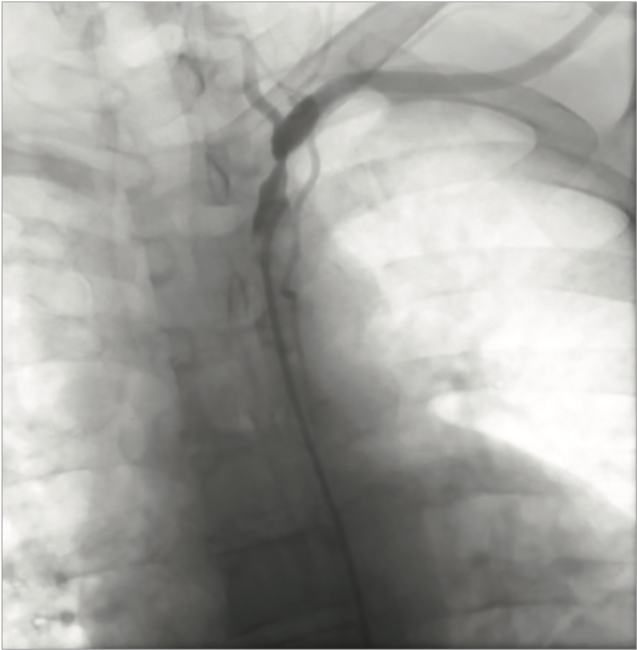

Long-Term Patency of a Drug-Coated Balloon in the Treatment of Upper Extremity Peripheral Artery Disease

Atherosclerosis is a systemic disease of the large- and medium-sized arteries causing luminal narrowing (focal or diffuse) as a result of the accumulation of lipid and fibrous material between the intimal and medial layers of the vessel.1 Non-coronary atherosclerotic vascular disease is called peripheral arterial disease (PAD), affecting approximately a half-million people within the United States. Up to half have symptomatic atherosclerotic lower-extremity disease. The prevalence of atherosclerotic peripheral arterial disease of an upper extremity is less common than lower-extremity disease. Percutaneous transluminal angioplasty and stenting have been a mainstay for the treatment of lower-extremity PAD. Treatment of PAD with a drug-coated balloon is an emerging technique.2 Drug-eluting devices inhibit neointimal growth of vascular smooth muscle cells with the potential of preventing restenosis.3 In the case herein, a drug-eluting balloon is used for the treatment of upper extremity atherosclerotic PAD.